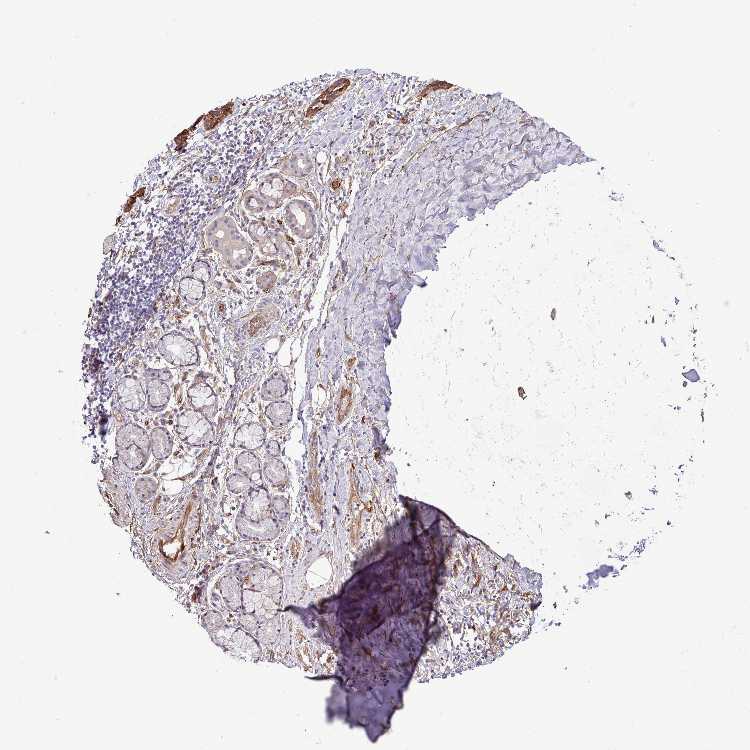

SOFT TISSUE 1 - Antibody stainingi

Antibody staining in the annotated cell types in the current human tissue is reported as not detected, low, medium, or high, based on conventional immunohistochemistry profiling in selected tissues. This score is based on the combination of the staining intensity and fraction of stained cells.

Each image is clickable and will lead to virtual microscopy that enables deeper exploration of all samples and also displays staining intensity scores, fraction scores and subcellular localization as well as patient and tissue information for each sample.

Antibody HPA041551Antibody CAB009733

Fibroblasts MediumMedium

Peripheral nerve -Low

SOFT TISSUE 2 - Antibody stainingi

Peripheral nerve HighMedium